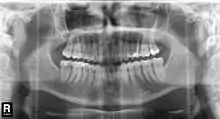

Histoire des rayons X dentaires

Le 23 janvier 1896, Wilhelm Röntgen présente à la société de physique médicale les rayons qu'il a nommés rayons X, qu'il a découverts en novembre 1895. C'est alors la main de l'anatomiste et physiologiste Albert von Kölliker qui sert d'objet pour la présentation. Après la présentation, Kölliker propose la dénomination de rayons Röntgen, alors que Röntgen les avait appelés jusqu'alors rayons X. Les deux désignations perdurent selon les aires linguistiques[126]. En janvier 1896 le dentiste Otto Walkhoff, dont Röntgen était patient, aurait fait les premières radiographies de dents, avec un temps de pose de 25 min[32]. L'utilisation de rayons X pour le diagnostic en médecine dentaire a été rendu possible par le travail de Charles Edmund Kells, un dentiste de la Nouvelle-Orléans, qui l'a présenté en juillet 1896 devant des dentistes à Asheville[127].

Antoni Cieszyński (1882−1941), médecin, dentiste et chirurgien polonais, considéré comme fondateur de la médecine dentaire polonaise, a mis au point la technique isométrique : pour minimiser les distorsions dans la radiographie d'une dent, il faut que les rayons soient perpendiculaires au plan bissecteur entre l'axe de la dent et le plan du film[128].

En 1934, le Japonais Hisatugu Numata met au point le premier appareil à panoramiques X dentaires. La mise au point de l'appareil intraoral, où le tube émetteur se trouve à l'intérieur de la bouche et le film à l'extérieur suit. En parallèle, Horst Beger, de Dresde, en 1943 et Walter Ott, dentiste suisse, en 1946 mettent au point les appareils Panoramix (Koch & Sterzel), Status X (Siemens) und Oralix (Philips)[129]. Le Finlandais Yrjö Veli Paatero (1901–1963) continue à mettre au point la technique et donne à l'appareil le nom de Parabolographie, puis de Pantomographie en 1950, et enfin sur la suggestion du Japonais Eiko Sairenji le nom Orthopantomographie en 1958[130],[131],[132]. Le premier de ces appareils est distribué en 1961 sous le nom de Panorex par la firme S.S. White[133]. Les tubes émetteurs et le film y tournent de façon synchrone autour de la tête du patient. À la fin des années 1980, les appareils panoramiques intraoraux sont abandonnés définitivement, parce que la dose de rayonnement par le tube en contact avec la langue et la muqueuse buccale se trouve trop élevée.

En 1987, Trophy Radiology (France) a mis sur le marché le premier appareil à rayons X numérique pour films dentaires sous le nom de Radiovisiographie. En 1995, DXIS, le premier appareil panoramique numérique est introduit par Signet (France), suivi en 1997 par SIDEXIS, (Siemens, plus tard Sirona) avec Ortophos Plus. Au lieu d'un film, les appareils contiennent un scintillateur, qui transforme les photons X incidents soit en lumière visible soit directement en impulsions électriques. Les données captées dans le détecteur sont renvoyées sous forme numérique à l'écran d'un ordinateur[134].